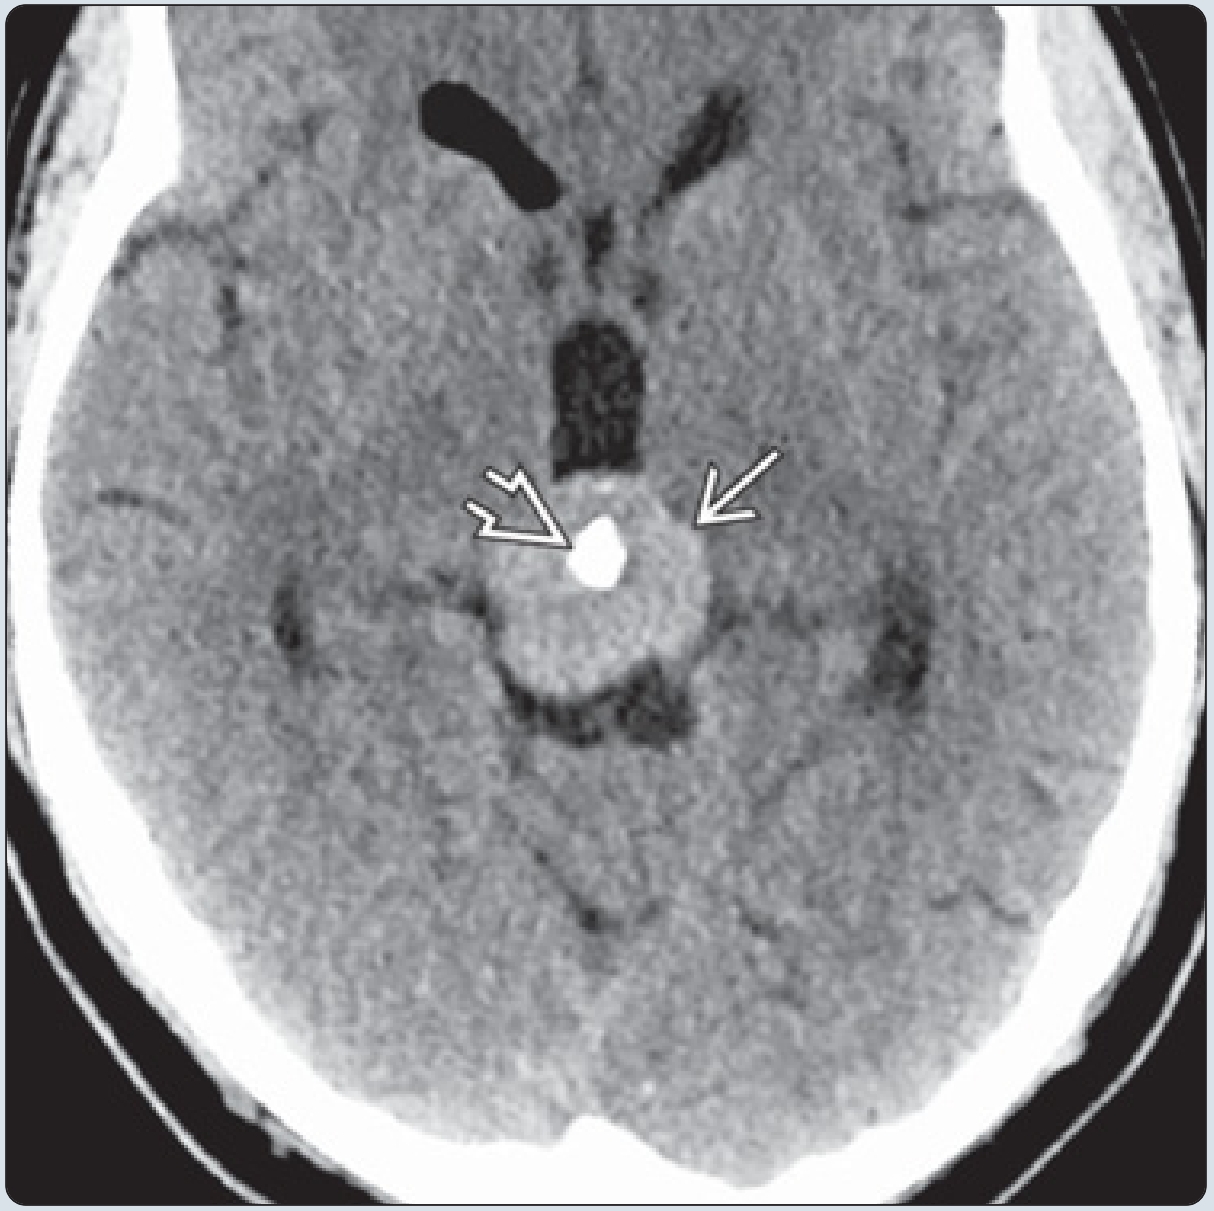

轴位CT扫描示典型的松果体生殖细胞瘤,可见边界清楚的稍高密度肿块包绕钙化的松果体。

• 实性为主,CT呈稍高密度,钙化少见;